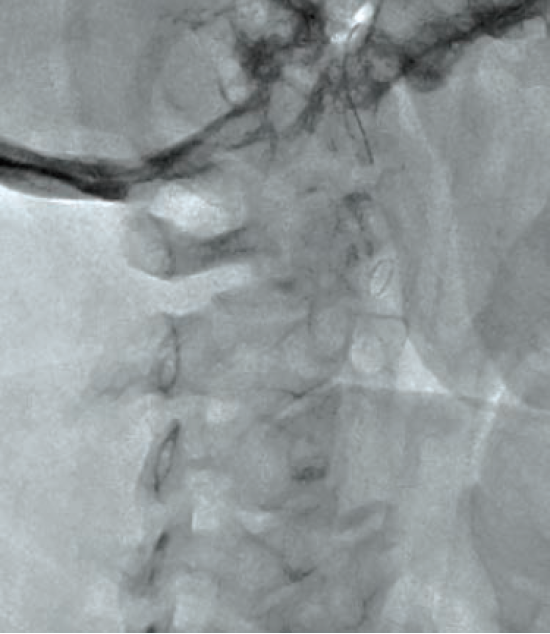

Following aseptic measures and under local anesthesia, a 7 French (Fr) right femoral access was obtained using a routine-length sheath. An .035-inch J-tip guide wire was then parked at the right common carotid artery (RCCA) using a 5 Fr Judkins right catheter, exchanged by a 7 Fr multipurpose guide. This was followed by advancement of a FilterWire EZ (Boston Scientific) across the ostial internal carotid artery stenosis, and deployed in the distal part of the extracranial ICA (Figure 2). After deployment of the FilterWire EZ, a direct stenting strategy was adopted to minimize thromboembolization. A 6 mm x 40 mm self-expanding stent was deployed at the RICA ostium (Figure 3). To our surprise, the view after stent placement showed zero flow into the distal RICA. (Figure 4) The reason appeared to be choking of the filter due to thromboembolization. The filter appeared to be overwhelmed by the volume of the debris captured. A 6 Fr Export catheter (Medtronic) was employed to suction debris from the distal ICA (Figure 5). We also administered pharmacotherapy using intra-arterial nitrate boluses and a weight-based tirofiban bolus. After these measures, there was fair flow into the distal ICA. During the period of no flow, the patient had transient hemispheric ischemic signs and an oropharyngeal airway was required, but his vitals remained stable. These symptoms rapidly resolved after establishment of ICA flow. After establishing blood flow, the proximal half of the stent that remained under-expanded was post dilated using a 4.5 mm noncompliant balloon at 12 atmospheres (Figure 6). Post dilatation, the angiographic view demonstrated good stent expansion and adequate distal flow (Figure 7). The distal protection device was then successfully removed using its retrieval sheath. The final DSA angiogram revealed excellent flow into the distal carotid (Figure 8A) and intracranial vasculature (Figure 8B), confirming no intracranial embolization. The guide was then safely removed over the .035-inch guide wire.